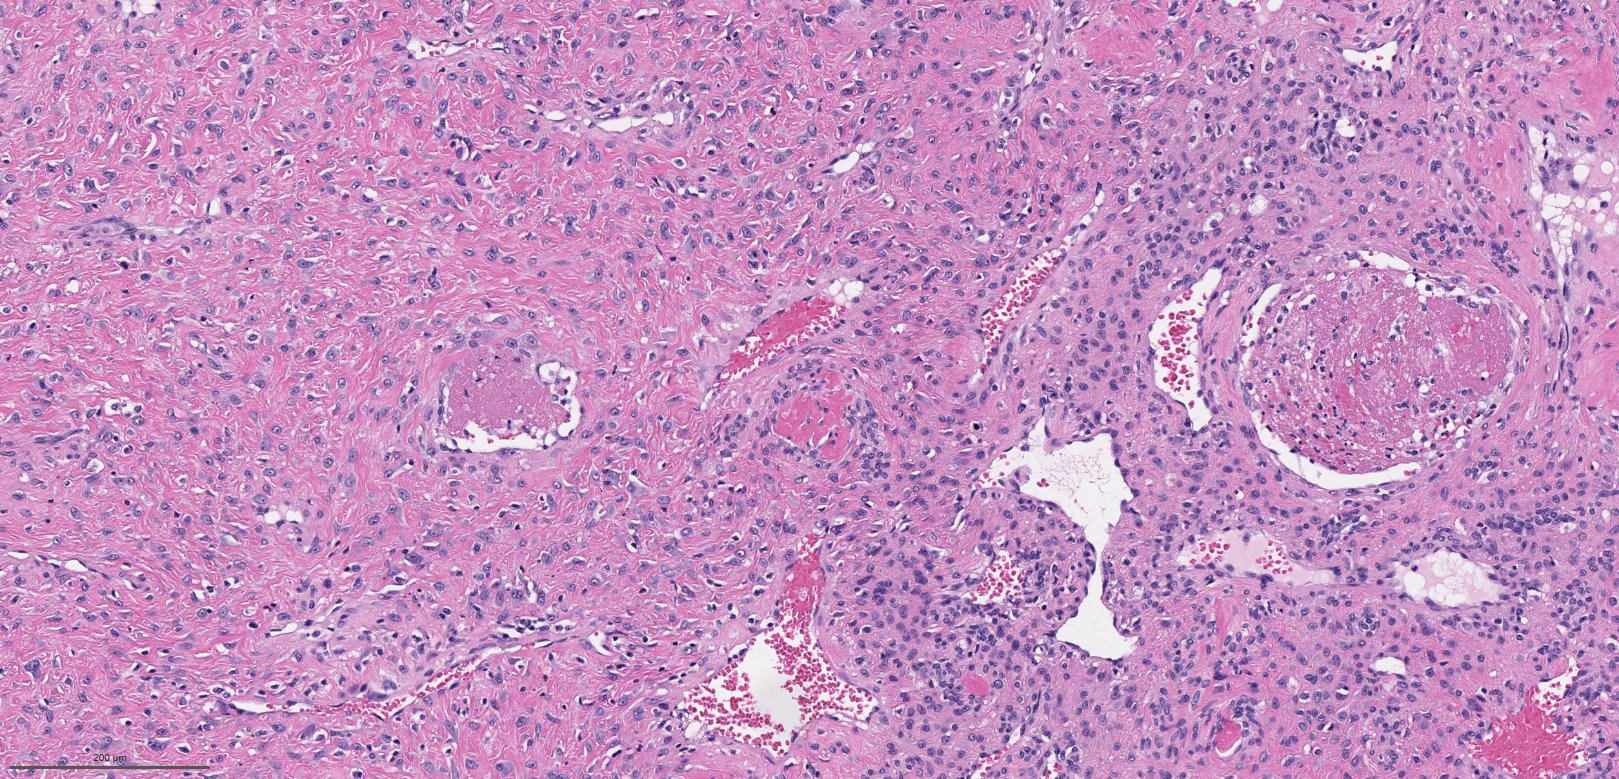

Microscopic (histologic) description

- Benign fibrovascular lesion composed of 2 components

- Vascular space of various sizes, ranging from dilated branching vessel of various thickness to slit-like capillaries

- Fibrous or collagenous stroma with fibroblasts

- Central area of the tumor is typically cellular, composed of fibroblasts or myofibroblasts with spindle, round or stellate morphology

- Stroma can be fibrous, edematous or collagenized

- Fibrinous thrombi may be seen in dilated vessels

- Frequently contain (abundant) mast cells

- Mitotic figures are usually absent

Microscopic (histologic) images

Contributed by Bin Xu, M.D., Ph.D.

Contributed by Kelly Magliocca, D.D.S., M.P.H.